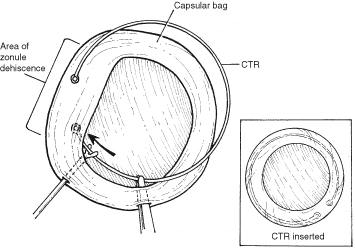

With lens removal, attention should first be paid to any prolapsed or incarcerated tissue. This should be repositioned or excised, and the corneal laceration should be sutured and the anterior chamber re-formed as described. The nature of the injury will suggest the surgical technique used for lens removal. If the lens capsule remains intact, standard phacoemulsification or extracapsular cataract extraction may be performed, making every effort to preserve the integrity of the posterior capsule. In children and young adults, a soft cataractous lens may be removed through a small incision using manual or automated aspiration. When extracting the nucleus in the patient post-trauma, one should be aware of the possibility of poor zonular support. Should zonular weakness, dialysis, or loss be present, a capsular tension ring (CTR) may be used. Implanting a CTR may decrease intraoperative zonule dehiscence, subluxation of the capsular bag, and posterior capsular rupture. A CTR inserted before phacoemulsification will permit support of the capsular bag, reestablishing its contour and protecting it from getting aspirated.14 The CTR (Morcher; distributed by FCI Ophthalmics, Inc., Marshfield Hills, MA) comes in three sizes and is usually inserted after capsulorrhexis and hydrodissection. For insertion, it is best to enter the bag in the area of greatest zonular weakness, thus placing stress on the stronger zonules, 180 degrees away. The ring is dialed into the bag using a second instrument (e.g., Y-hook) (Fig. 14). Alternatively, a CTR injector may be used.